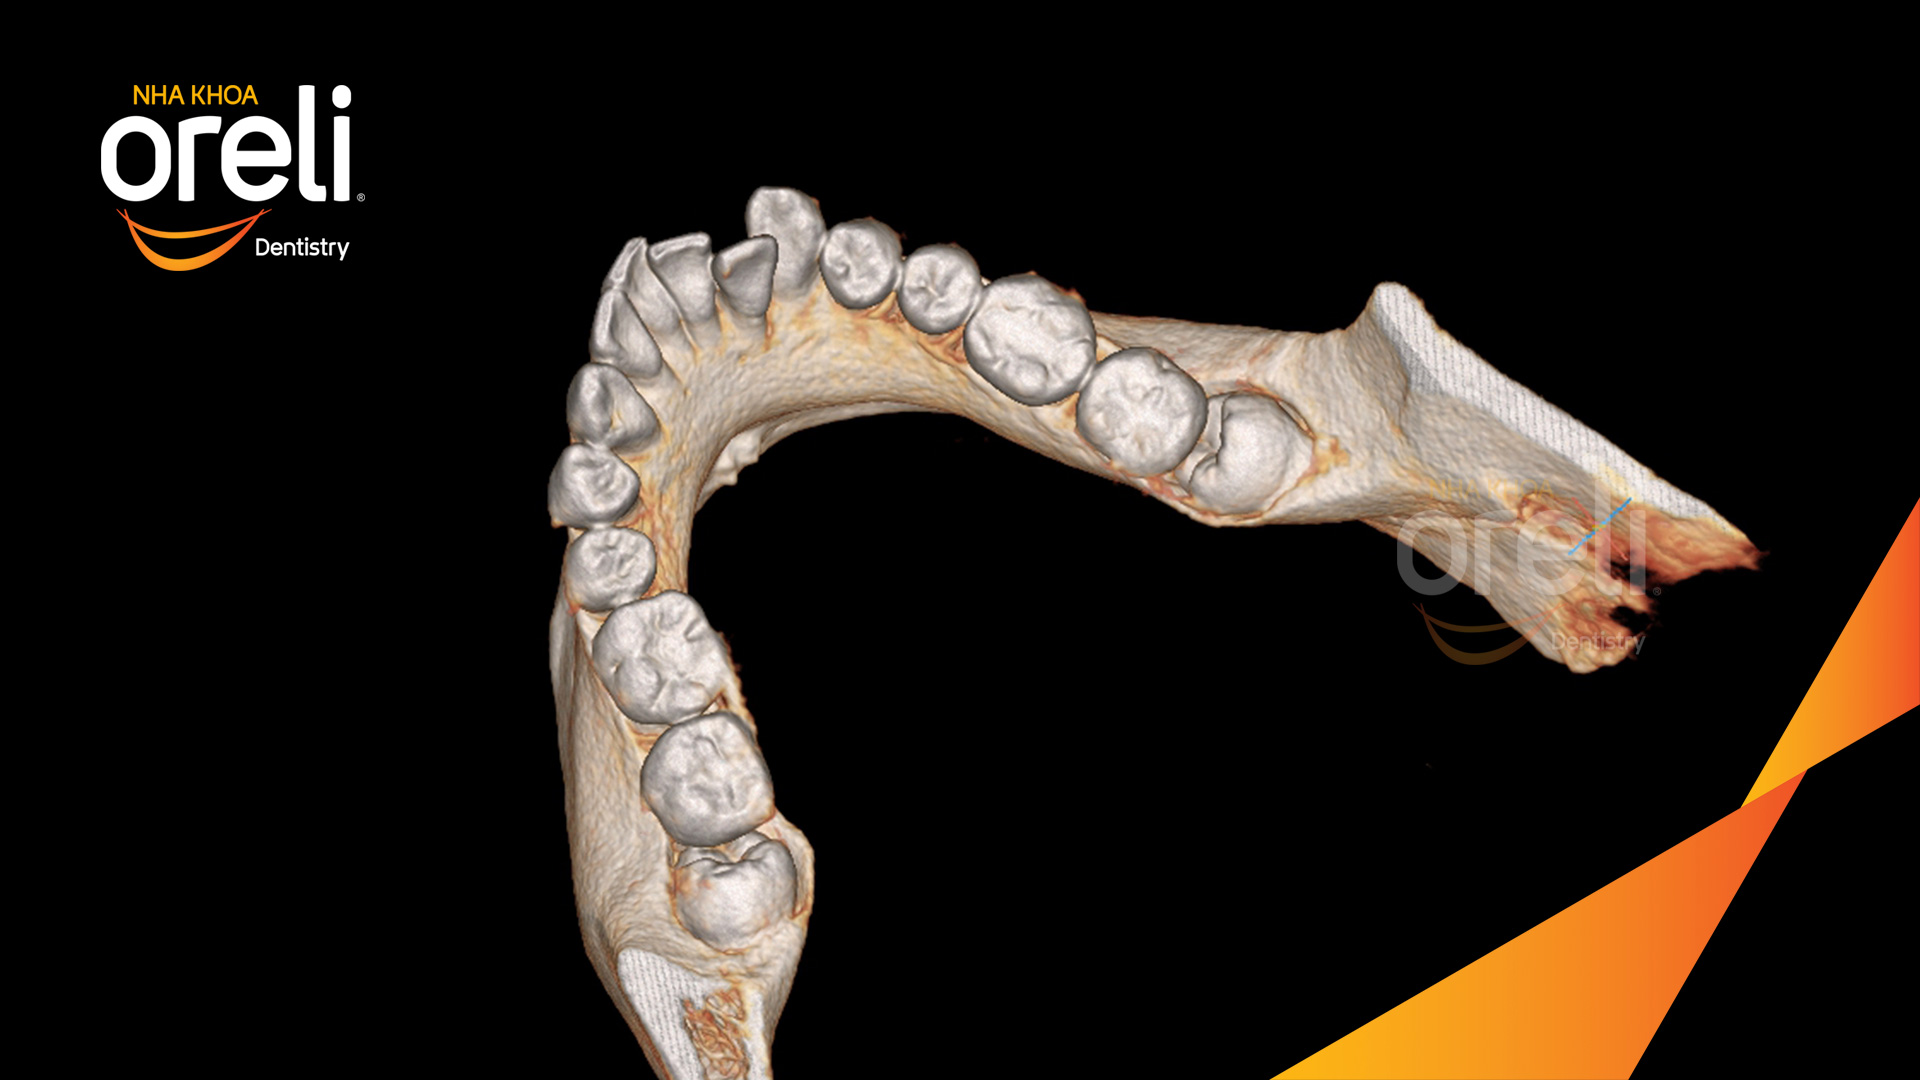

Ca nhổ răng khôn ảnh hưởng răng bên cạnh – Điều trị tại Oreli

Nhổ răng khôn

Mọc lệch